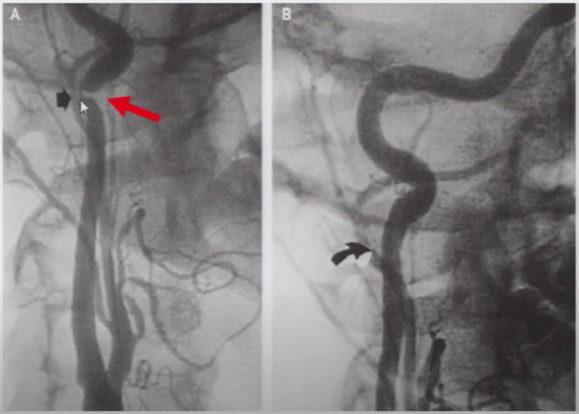

➤ 颈动脉体瘤合并FMD

图9 一位54岁女性,因为颈动脉体瘤而行术前DSA检查,显示并存的纤维肌发育不良